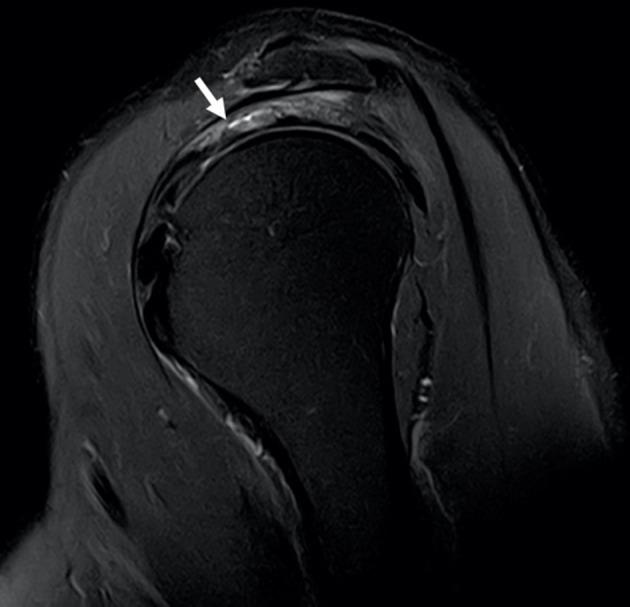

Myotendinous junction tear of the anterior bundle of the supraspinatus muscle-a rare pattern of injury involving rotator cuff muscles.

Myotendinous junction injuries are rare and often present with distinctive imaging findings that should be differentiated from purely tendinous degenerative ruptures. Myotendinous junction tears are common in the lower limb but rarely involve rotator cuff muscles. Considering rotator cuff muscles, the infraspinatus and supraspinatus muscles are the most frequently implicated. The intrinsic anatomy of the supraspinatus muscle gives it a greater contractile force and consequently a propensity for rupture. It is composed of two bundles: anterior and posterior (with the latest further divided in a deep anterior, a medial and a superficial posterior portion). These two components have distinctive anatomy with the anterior bundle having a long intramuscular tendon and bipennate configuration and the posterior bundle having a smaller intramuscular tendon and parallel muscle fibres. This distinctive anatomy grants a greater contractile force to the anterior bundle of the supraspinatus muscle and for this reason it is more prone to myotendinous rupture. This type of injury has been associated with a rapid progression to severe fatty infiltration and should be differentiated from purely tendinous tears that are more frequent and associated with degenerative changes. Myotendinous tears occur centrally located in the muscle belly and are not associated with full thickness tears of the distal tendon attachment.